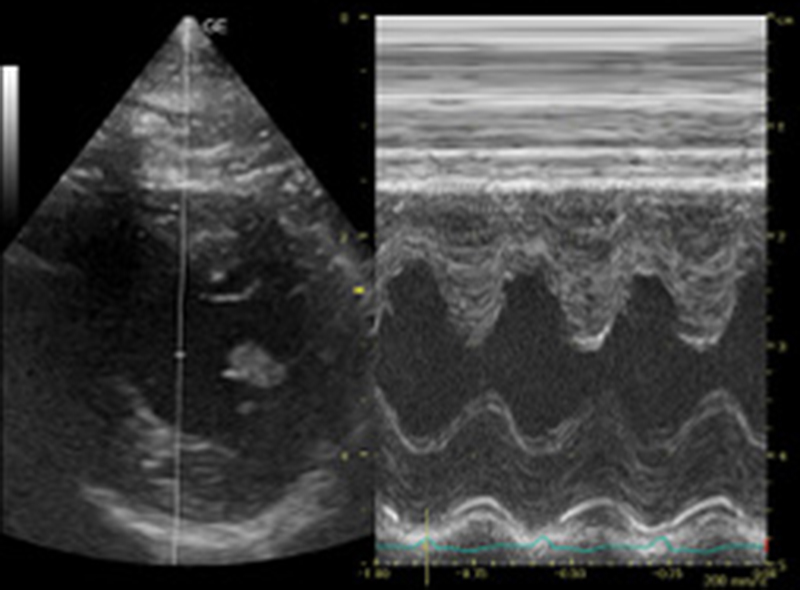

超音波検査

レントゲン検査や血液検査、触診で異常がある場合には追加検査としてお勧めしています。

動的な状態で検査できること、臓器の内部構造がわかることなどの利点があります。

動かないように押さえて、少し時間をかけて検査しますので、場合によっては後日予約制で検査を行います。

循環器の疾患

僧帽弁閉鎖不全症

胸部レントゲン検査、超音波検査、血液検査(特殊項目)

肥大型心筋症・動脈血栓塞栓症

猫・中年齢以降で見られ、心臓の壁が分厚くなってしまう病気です。この病気は、だいぶ進んで、突然、後肢を引きずり、ギャアギャア泣き喚くなどの症状を呈して初めて気づくこともあります。こういった症状を呈する前に検診でそのリスクを発見することもできます。

難しい病気になりますが、僧帽弁閉鎖不全症や呼吸器疾患に合併したり、特発性に起こることがあります。症状は咳やチアノーゼなどが見られます。診断は、超音波検査により基礎疾患とともに精査します。